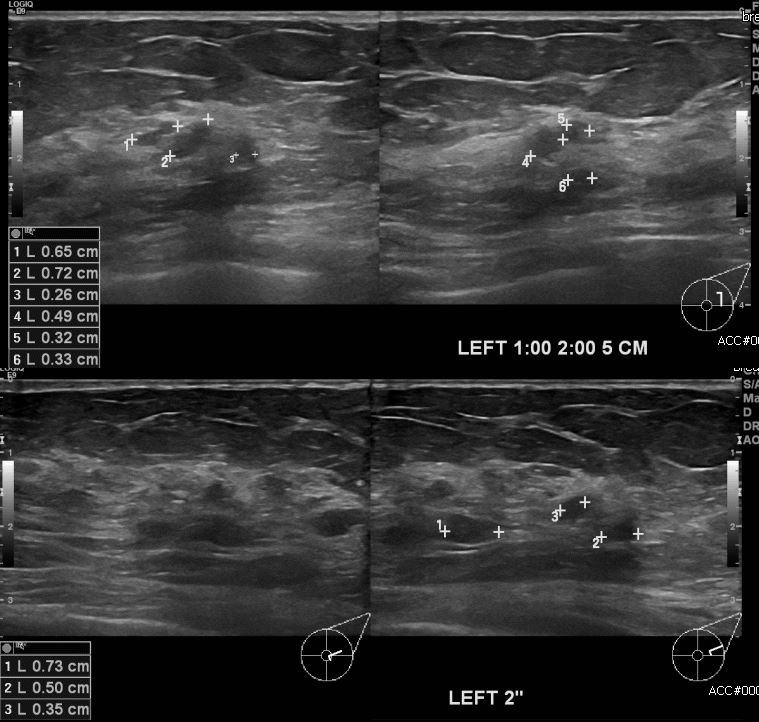

건강검진상 이상 소견으로 내원하신 70대 여성분으로  좌측 유방에 의심 스러운 부분

조직검사 시행하여 좌측 유관암 진단 되었습니다.